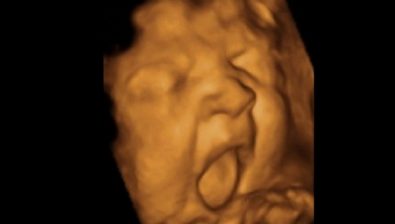

Ultrasound at 38 Weeks

Your baby’s head circumference and waist circumference are around the same size this week.

Your baby is ready for birth but might want to hide out in your uterus for a little bit longer.